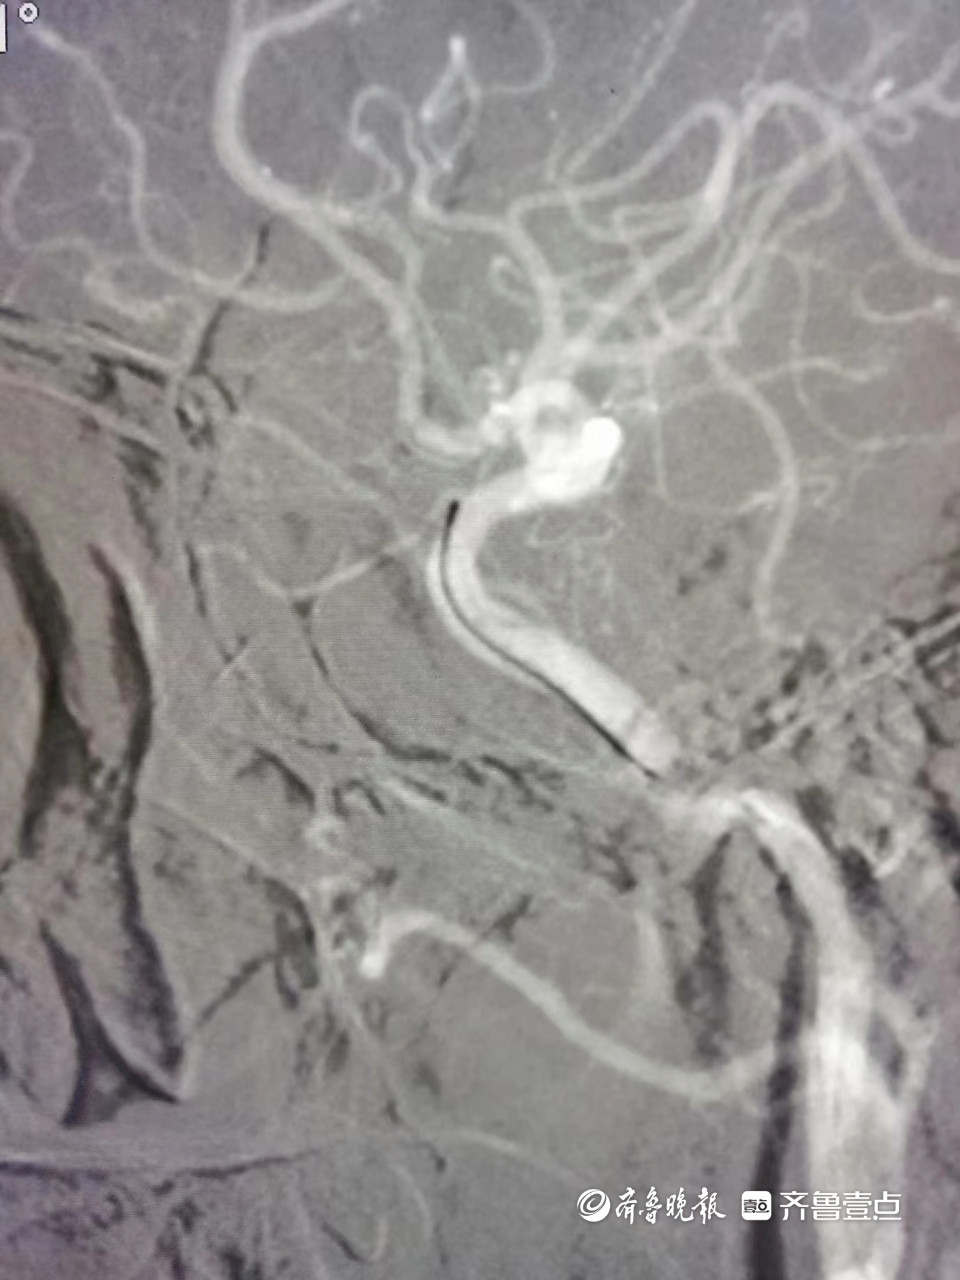

手术眼科与神经介入科共同实施。介入治疗采取神经介入科贺西亮主任开展的新技术——经桡动脉入路的血管造影进行。经桡动脉通路,也就是在胳膊上打一针,对病人影响小、痛苦小、术后不影响生活。经过血管的造影检查,发现张先生其他部位的血管也存在一定程度的病变,同时眼动脉的视网膜中央动脉分支明显血流不足。眼动脉是颈内动脉进入大脑后发出的第一支血管,它的位置和颈内动脉垂直。如何进入眼动脉内,这是超选眼动脉溶栓治疗的难点。在明确病灶后,贺西亮主任用一根头发丝一样细的微导丝超选把一根纤细的微导管放置在眼动脉内,准确注入了溶栓的药物。经过眼科OCT的检查,术后两个小时视网膜的血流相较于术前已经有明显的改善,张先生视力逐渐恢复。